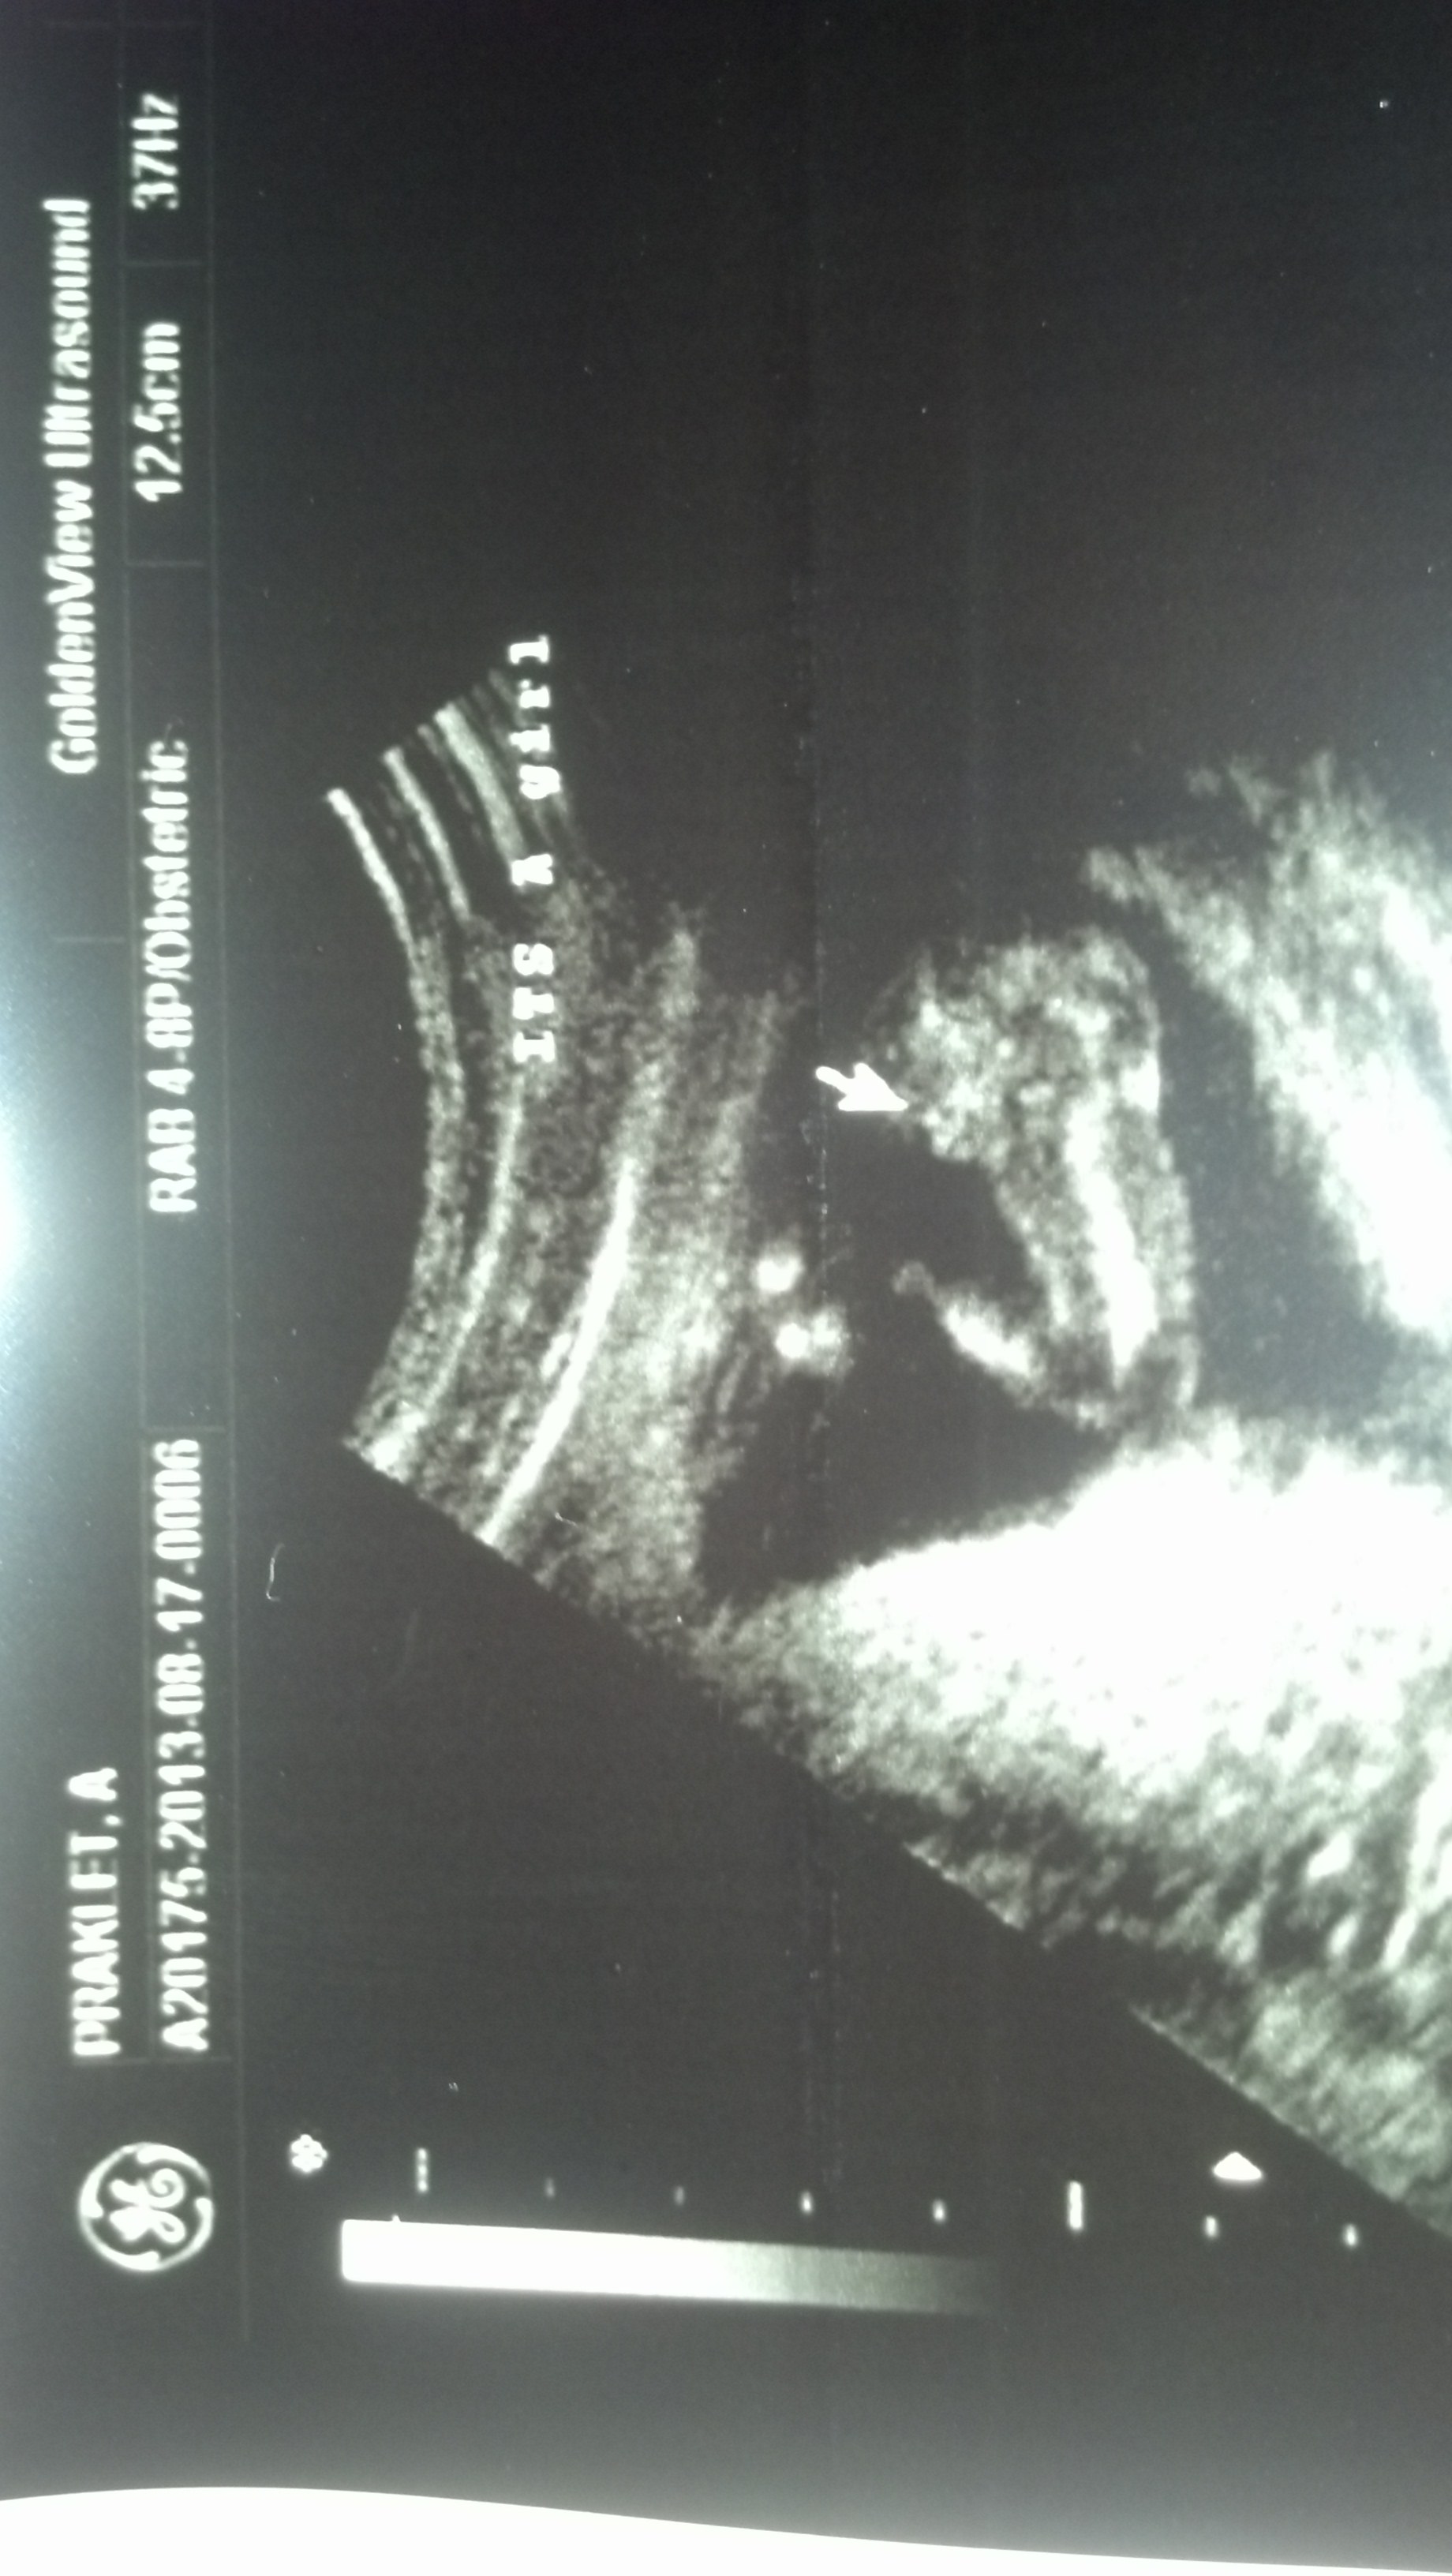

Attachment 14320Attachment 14321